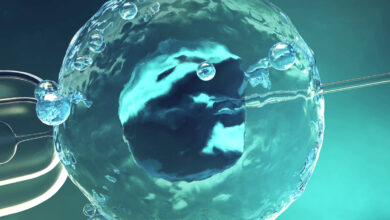

التقنيات المساعِدة على الحمل… اختيار التقنية الأنسب يعتمد على سبب عدم الإنجاب

التقنيات المساعِدة على الحمل… اختيار التقنية الأنسب يعتمد على سبب عدم الإنجاب يعتبر الحقن المجهري وأطفال الانابيب من أشهر التقنيات…